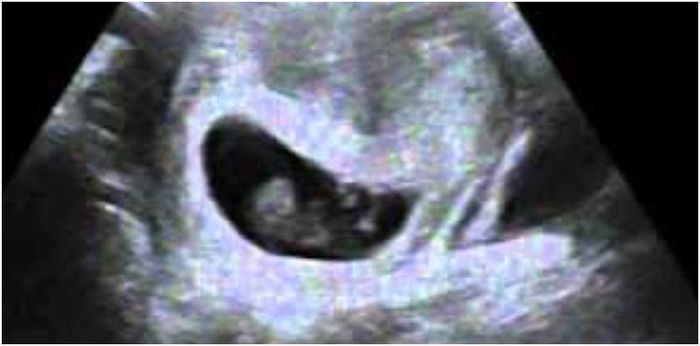

In the earlier days, before ultrasound was available, the diagnosis of the death of a twin or multiple was made through an examination of the placenta after delivery. Today, it is possible to diagnose vanishing twin syndrome with an ultrasound.

For example, a mum-to-be may have an ultrasound at 6 or 7 weeks gestation. The doctor identifies two foetuses and tells the mother she is having twins. When she returns for her next visit though, it is possible that the doctor only hears one heartbeat, and a second ultrasound reveals the presence of only one foetus in the uterus.

Then the diagnosis is given as vanishing twin syndrome after the heartbeat of the twin or multiple can no longer be detected.

This is why getting your check-up is important, as the ultrasound may reveal a vanishing twin diagnosis.